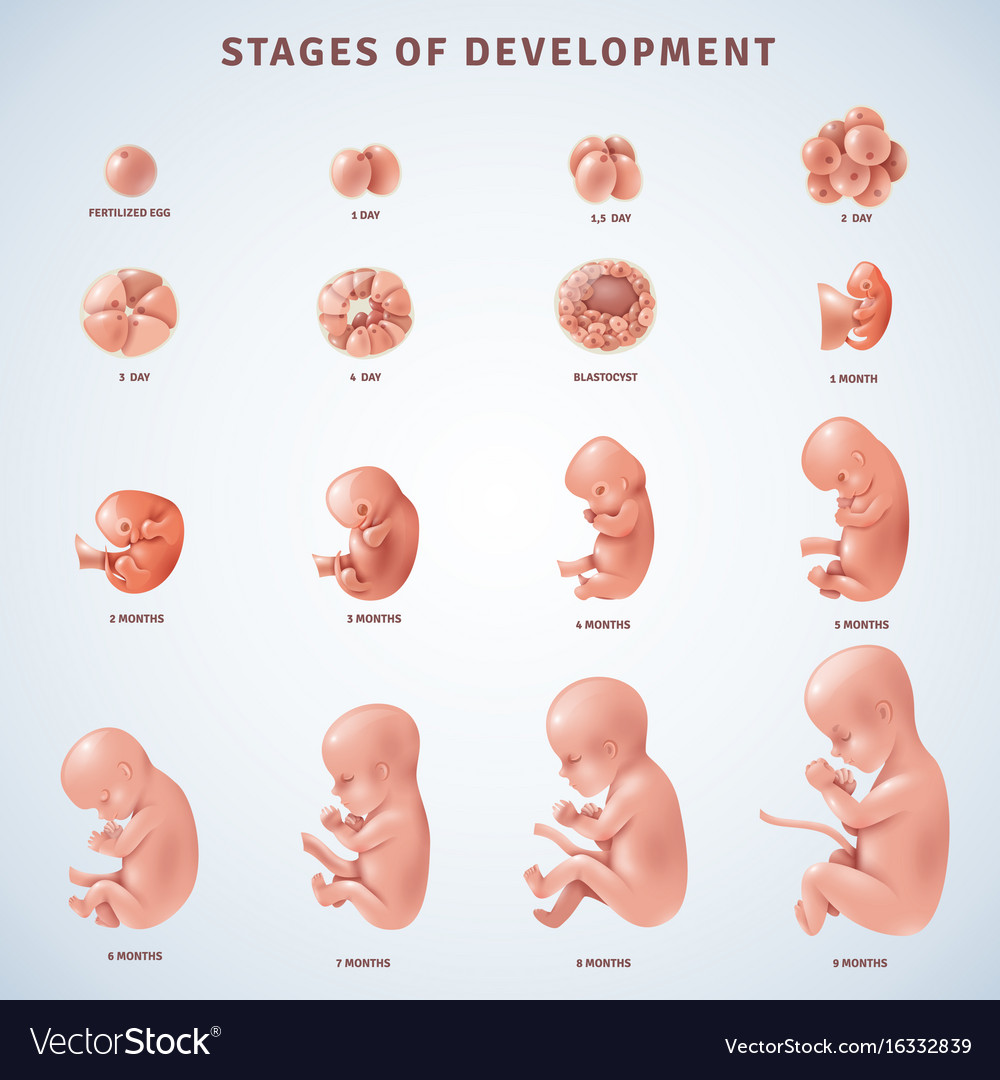

what does a 2 month old fetus look like

Posts: what does a 2 month old fetus look like